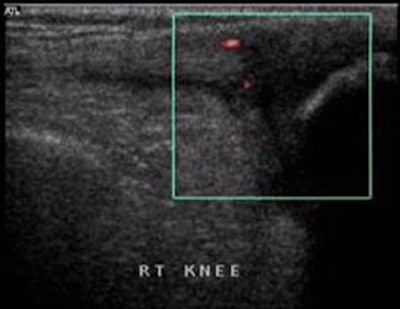

![]() |

| PDS shows markedly increased vascularity. |